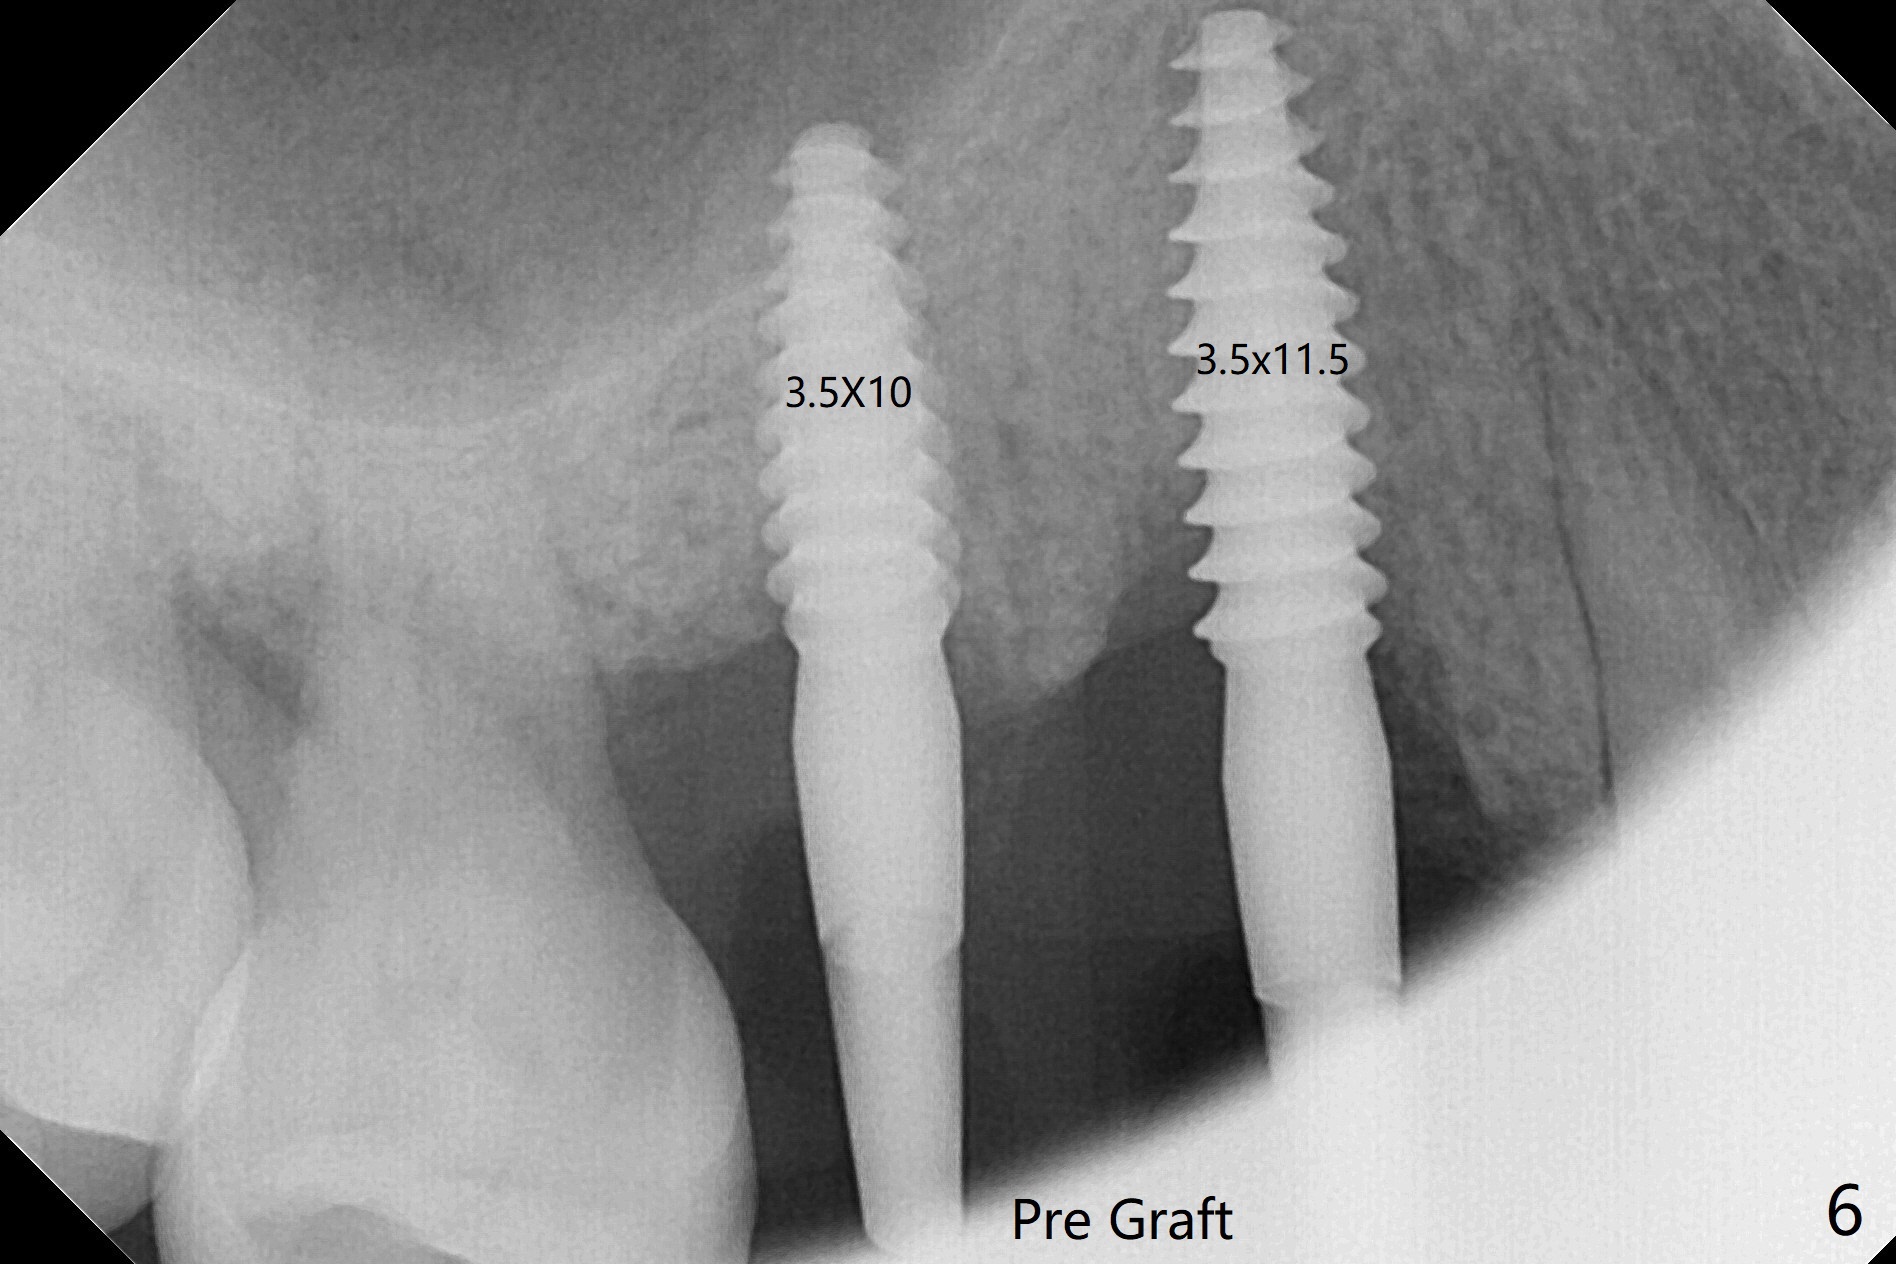

术前CT显示右上4牙槽骨比5窄(图一,二),3.5毫米植体比较合适,况且牙龈厚,基台长的一段式植体显得得当。为了取得最好的植体方位,4先拔除(图三),种植(图四),调整后者深度后,拔除5(术前征求病人同意),开始钻洞(图五),完成种植(图六)。粘性骨粉不仅放置于植体周围,而且6牙根近中(图七),4/5牙槽嵴和龈乳头(P)之间,减少术后龈乳头萎缩(图八:*)。制作两个分开临时牙冠,有利于维持龈乳头。对于病人来说,临时牙冠帮助咀嚼,而对侧拔牙创无法吃饭。术后3个月两个分开临时牙冠(其中一个龈方移位(图九:箭头)保持龈乳头(*)和牙龈外形(图十:*)。临时牙冠取出后,调整基台高度,少量钛屑(不妨大局)附着在健康的牙龈沟(图十一),再次显示两个基台之间龈乳头(图十二:*),衬里,修整的临时牙冠又插回牙龈沟(图十三:箭头),继续维持软组织形态,准备一个月后,调整基台边缘(图十二:箭头),取模。术后五个月大部分骨粉依然保留在植体和邻牙周围,龈乳头退缩不多(图十四: P)。三个月后(术后六个月)钛削无影无踪(图十五,与图十一对比))。永久性牙冠周围空间慢慢会消失(图十六,使用临时性胶水)。